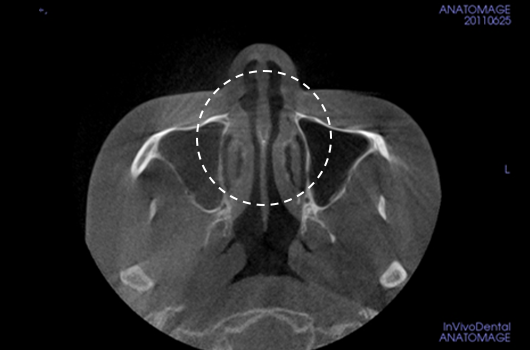

3. Analysis of the width and asymmetry of the nasal bone

Analysis of the width and asymmetry of the nasal bone